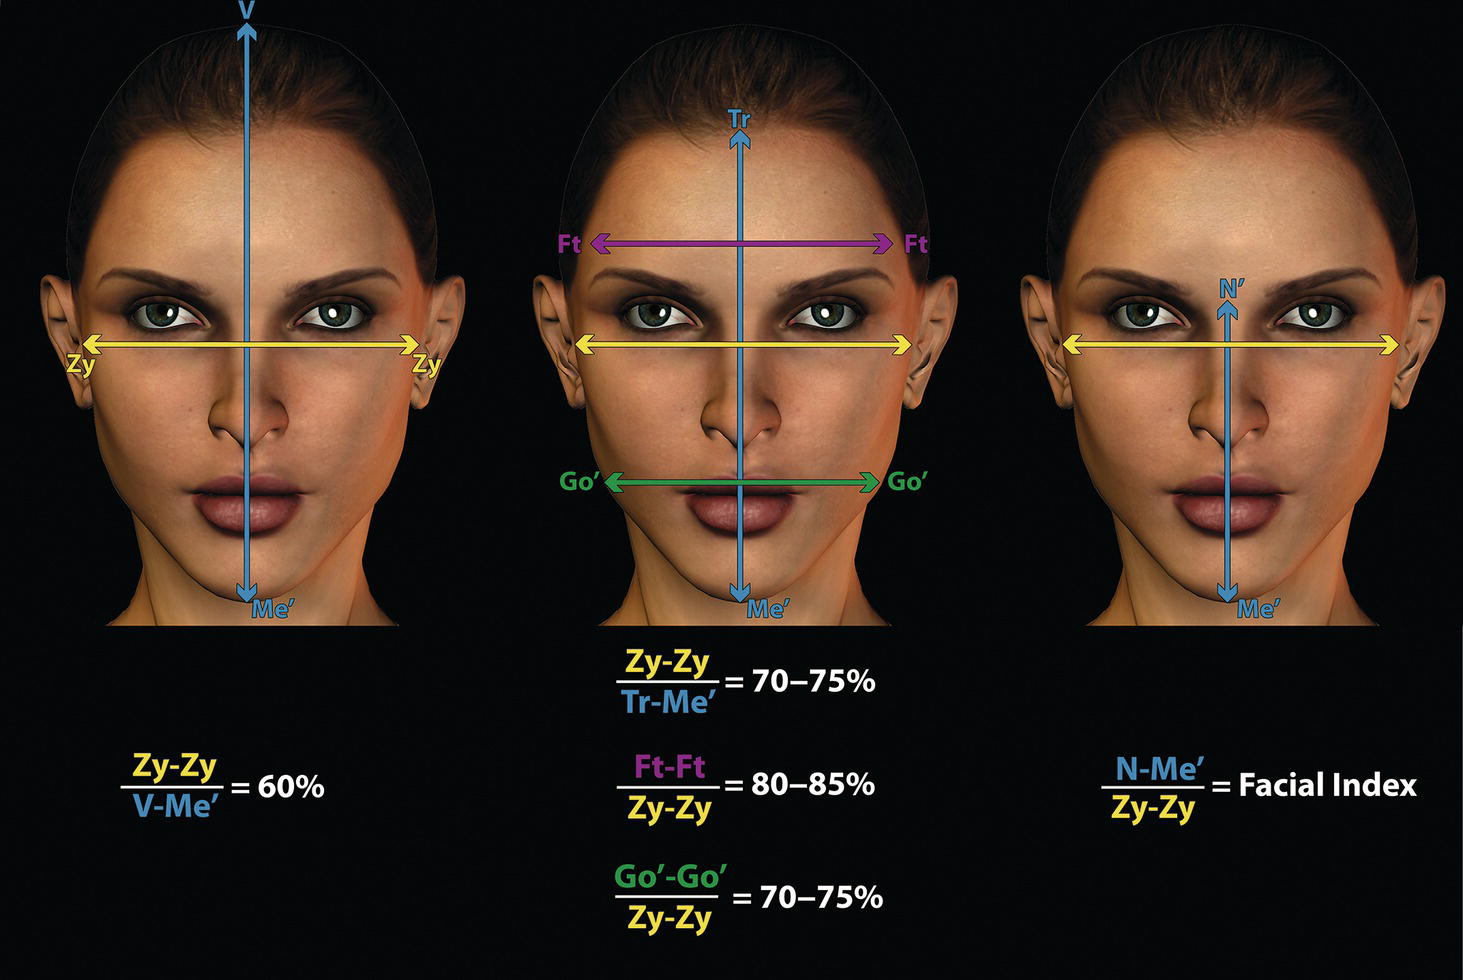

‘It is the common wonder of all men, how among so many millions of faces, there should be none alike’. Sir Thomas Browne (1605–82), English physician and writer, Religio Medici (1643)1 Individual variability is a fundamental principle in human biology. One of the most variable and distinguishable parts of the human body is the craniofacial complex. Clinicians will often compare a patient’s craniofacial measurements and proportions to the so‐called population norms (normative values) or even to classical ideals. However, Simon (1926) stated: ‘all we ever find are variations; an exact, ideal normal does not exist, cannot exist. And this is our enigma; in theory we will never find the normal, in practice we forever feel its need and apply it constantly’.2 The use of population norms may be logically enhanced by evaluating normal ranges of variability. Therefore, clinicians must have a thorough understanding of the normal ranges of variability in every aspect of craniofacial form, depending on age, sex and ethnic variability. Developmental disorders, as well as traumatic injuries and pathological conditions, may lead to deformities of the head and the face. Therefore, clinicians need to have a thorough understanding of the normal anatomy and morphological range of variation of the craniofacial complex in both males and females of different ages and ethnic groups, to act as guidelines when treatment planning the restoration of normal craniofacial proportions. Classifications that are useful for descriptive purposes include: A proportion index provides a numerical expression of the proportionality of a region of the craniofacial complex. The use of proportion indices dates back through the history of craniometry, particularly in the late nineteenth century. Linear (chord) or surface (arc) distances of the skull were measured between a variety of defined craniofacial landmarks; with any two measurements, the smaller was expressed as a percentage of the larger in order to provide a proportion index value. These could be used to provide an indication of skull shape. Figure 8.1 Determination of the normality or abnormality of any craniofacial measurement (or proportion index value) obtained from patients may be evaluated by comparison with the normative values obtained from a normal (average representative) population sample. The normal range of measurements is provided by the mean ±2 standard deviations (SD). The shape of the normal distribution curve shown is determined by the population standard deviation. Craniofacial parameters with small SDs have narrow, taller curves and those with large SDs have broader, flatter curves. Approximately 68% of all values fall within the range of ±1 SD from the mean and 95% within the range of ±2 SD from the mean. The normal range of variability for any craniofacial parameter is taken as being equal to the mean ±2 SDs. Greater differences may be perceived as deformities of gradually increasing severity. The leading researcher in the field of craniofacial anthropometry from the mid‐1960s to the early 2000s was Leslie Farkas, from the University of Toronto. Farkas et al. collected a large quantity of highly relevant anthropometric data between 1968 and 1984, from 2564 individuals.3 These data were used to provide 166 individual facial ratios, presented as proportion indices. In the creation of an index, the smaller measurement is multiplied by 100 (numerator) and divided by the larger measurement (denominator). Thus, a proportion index involves two linear craniofacial anthropometric measurements, with the smaller being expressed as a percentage of the larger. Proportion indices permit objective, quantitative assessment of facial morphology and proportions. Farkas3 identified two basic categories of proportion indices: Each proportion index will have a mean index value and a range of variation for a given population group, based on age, sex and ethnicity. The standard deviation (SD) determines the normal (average) range of variability of an index, from 2 SD below to 2 SD above the mean. Index values within this normal range are regarded as variations of normal proportions.4 Measurements within ±1 SD of the mean are regarded as optimal. The relationship between two measurements is disproportionate if the proportion index value is outside the normal range (Figure 8.1).4 For a number of facial parameters, single morphological measurements or proportion index values may have a large SD and, therefore, wide normal ranges of variation; as such, only measurements or proportion index values which differ considerably from the mean of the population will be perceived as deformities. Conversely, other facial parameters may have very small normal ranges of variability, in which case even a small difference from the mean may be perceived as a deformity. The cephalic index (index cephalicus) is a numerical expression of the ratio between the head width (biparietal diameter) and head length (fronto‐occipital diameter) of a living person. The cephalic index (CI) is calculated by the formula (Figure 8.2): Figure 8.2 Cephalic index. Where: The cephalic index is used in anthropometry to classify head types as (Table 8.1; Figure 8.3): Table 8.1 Classification of anatomical head types Index values according to Martin and Saller.5 Figure 8.3 Head types. The highest cephalic index values occur in the Chinese and the lowest values in African Americans. The larger index values of the Chinese differ significantly from those of whites or blacks (Table 8.2).6 A comparison of the cephalic index values of three ethnic groups was undertaken; North American Caucasians, northern European (German) and eastern European (Czech). The index values indicated a mesocephalic head type for both sexes of North American Caucasians and northern Europeans; and a brachycephalic (short‐wide) head type for the eastern Europeans.6 The head circumference is measured in the horizontal plane around the head, through the glabella and opisthocranion. However, it may be measured across ophyron (the point ‘On’, in the mid‐sagittal plane, of a line tangent to the upper limits of the eyebrows) rather than glabella in order to eliminate the effect of development of the frontal sinuses and superior orbital rims on head circumference.5,7 African Americans have the largest and the Chinese have the smallest head circumference for both sexes. The head circumference is slightly larger for blacks than for whites for both sexes.6 The initial step in facial analysis involves the examination of the face in frontal view in order to assess the overall facial shape. The variety of facial shapes is almost limitless. However, a simple assessment will allow an overall categorization of the basic facial shape. The basic facial shape in frontal view may be any combination of the following: Table 8.2 Cephalic index of three ethnic groups Data modified from Farkas.6 SD = standard deviation. Table 8.3 Head circumference of three ethnic groups Data modified from Farkas.6 SD, standard deviation. Figure 8.4 Facial height‐to‐width ratios. Variations in facial height and width result in an innumerable variety of the three basic facial shapes (round, square and triangular). For example, an oval facial type is a combination of an overall round face combined with increased vertical facial height and/or reduced facial width. The relationship of vertical facial height to facial width is an important indicator of overall facial shape. There are three methods of evaluating the vertical facial height‐to‐width proportion. These may be presented as proportions, percentages or indices: The facial index (index facialis or index of the morphological face height) is a numerical expression of the ratio between the facial height (nasion to menton) and the bizygomatic facial width (zygion to zygion) of a living person. The facial index (FI) is calculated by the formula: Where: The facial index is used in anthropometry to classify faces as (Table 8.4; Figure 8.6): Figure 8.5 Facial types according to Albrecht Dürer. (Modified from Dürer, 15288.) Figure 8.6 Facial types. Table 8.4 Classification of anatomical face types Index values: male according to Garson, 1885;9 and female according to Martin and Saller, 1957.5 The term facial divergence was introduced by the orthodontist‐anthropologist Milo Hellman,10 although the concept had been described by Albrecht Dürer (1528) (Figure 8.7).8 It is essentially a description of the slope or inclination of the face in the sagittal plane (Figure 8.8). It is determined by the sagittal position of soft tissue pogonion (Pog’) and subnasale (Sn) relative to a vertical line dropped from glabella (G’), with the subject’s head in natural head position. The factor that discriminates and distinguishes facial divergence from profile convexity or concavity is the sagittal position of subnasale (Sn) relative to the G’‐Pog’ line. In order for the face to diverge anteriorly or posteriorly, yet not to exhibit signs of convexity or concavity, subnasale (Sn) must be on or nearly on the G’‐Pog’ line; i.e. the upper facial plane (UFP, G′‐Sn) and the lower facial plane (LFP, Sn‐Pog’) are in a straight line, but diverge anteriorly or posteriorly. Figure 8.7 Facial divergence according to Albrecht Dürer. (Modified from Dürer, 15288.) Figure 8.8 Facial divergence. Anthropometric data from North American Caucasian males and females with untreated Class I dental occlusions describing normal facial divergence and ranges of variability has been provided.11 Mean values of facial divergence are negative, with the faces being slightly posteriorly divergent. Anterior divergence does not occur until two standard deviations from the mean. Facial divergence is essentially an ethnic variation in facial profile form. With a straight profile, i.e. no excessive profile convexity or concavity, anterior or posterior facial divergence is compatible with a normal maxillo‐mandibular and dental occlusal relationship. Figure 8.9 Facial profile contour according to Albrecht Dürer. (Modified from Dürer, 15288.) Figure 8.10 Facial profile contours. The contour of the facial profile may be described as convex, straight or concave. This concept was described by Albrecht Dürer (1528) (Figure 8.9).8 With the patient in NHP, the overall contour of the facial profile may be described by the relationship between two lines: the upper facial plane (UFP), connecting glabella (G’) to subnasale (Sn), and the lower facial plane (LFP), connecting subnasale to soft tissue pogonion (Pog’). In a straight profile, these two lines form a nearly straight line. Such a facial profile is termed orthognathic (Greek orthos: correct or straight; gnathos: jaw). An angle between these two lines indicates facial profile convexity (pogonion behind relative to subnasale in the sagittal plane), or facial profile concavity (pogonion ahead relative to subnasale in the sagittal plane). A convex profile indicates a skeletal Class II jaw relationship (and/or sagittal chin deficiency), and a concave profile indicates a skeletal Class III jaw relationship (and/or sagittal chin excess). However, profile convexity or concavity does not of itself indicate whether the maxilla or mandible/chin is at fault (Figure 8.10). Legan and Burstone12 described the angle of facial convexity for the soft tissue profile. It is formed by the two intersecting lines, the UFP (G′‐Sn) and the LFP (Sn‐Pog′). The mean value is estimated to be 12° ± 4°. An increase in the angle in a clockwise direction is positive; anticlockwise is negative. A high positive value suggests facial profile convexity and a Class II skeletal jaw relationship; a smaller positive value, or a negative value, suggests facial profile concavity and a Class III skeletal jaw relationship. However, the value of this angle does not reveal whether the maxilla or mandible/chin is responsible for the sagittal jaw discrepancy. Figure 8.11 Angle of facial profile convexity (facial contour angle). Downs13 described the angle of convexity, formed by the intersection of line nasion to point A (NA) and line point A to pogonion (A‐Pog). Superior extension of the A‐Pog line forms an angle with the NA line; if behind the NA line, the angle is read as positive, indicating a Class II (convex) skeletal profile. A negative angle of convexity indicates a Class III (concave) skeletal profile. Downs provided a range of values from −8.5° to 10°, with a mean of 0°. Again, as with the facial contour angle, the angle of convexity does not determine the localization of the deformity to the maxilla or mandible/chin. An investigation was carried out with the objective of assessing how lower facial profile convexity influences perceived attractiveness. The lower facial profile of an idealized image was altered incrementally between 14° and −16°, creating a range of images which were evaluated by pretreatment orthognathic surgery patients, laypeople and clinicians. A straight profile was perceived as most attractive and greater degrees of convexity or concavity deemed progressively less attractive, but a range of 10° to −12° was deemed acceptable; beyond these values surgical correction was desired. Patients were most critical, and clinicians were more critical than laypeople.14 The facial angle indicates the relative sagittal prominence of soft tissue pogonion. It is formed by the intersection of the true horizontal plane (or Frankfort Horizontal plane) with a facial vertical plane (N′‐Pog’). The angle should be approximately 90°–92°. A greater angle indicates prominence of soft tissue pogonion; an angle less than 90° indicates retrusion of soft tissue pogonion. The soft tissue facial angle does not of itself determine the aetiology of the sagittal position of soft tissue pogonion, which may be due to one or a combination of: Consequently, the facial angle must be used in conjunction with other measurements and analyses. In addition, when constructing the facial vertical line (N’‐Pog’), if the sagittal position of nasion is not acceptable, it may be adjusted to a more ideal position. The alternative is to use soft tissue glabella (G’) rather than nasion. Downs13 described the facial angle as the inferior inside angle in which the facial line (N‐Pog) intersects the Frankfort Horizontal plane. Downs found a mean value of 88° with a range of 82°–95°. It indicates the relative sagittal position of the mandible/chin to the upper face. Figure 8.12 Facial angle. FH, Frankfort Horizontal plane; TrH, true horizontal plane. Figure 8.13 The relationship of the cranial base angle (saddle angle) and anterior cranial base length on the jaw relationship. The relationship of the anterior to the posterior cranial base is of particular importance in the diagnosis of facial profile contour. This relationship depends on the extent of growth at the sphenoethmoidal and spheno‐occipital synchondroses. The cranial base angle (or saddle angle) represents the orientation of the anterior cranial base (SN line) relative to the posterior cranial base (S‐Ba line).15 The average adult values (bearing in mind that there is negligible change in this angle after the age of six years) for the angle N‐S‐Ba are16: As such, the cranial base angle is an important determinant of craniofacial form, as it influences the sagittal position of the face relative to the neurocranium and the sagittal prominence of the mandible relative to the maxilla. A significantly increased cranial base angle contributes to a skeletal Class II jaw relationship, whereas a reduced cranial base angle contributes to a skeletal Class III jaw relationship. If basion is difficult to identify on a lateral cephalometric radiograph, articulare may be used instead, i.e. the posterior cranial base is drawn between sella and articulare. The average adult values for the angle N‐S‐Ar are16: The anterior cranial base length, measured from sella to nasion, may also influence the jaw relationship. For example, increased anterior cranial base length may lead to a Class II jaw relationship, with the maxilla ahead of the mandible in the sagittal plane, whereas reduced cranial base length may lead to a Class III jaw relationship, with the maxilla behind the mandible in the sagittal plane. The average adult values for the anterior cranial base length are16: Figure 8.14 Parasagittal profile contour. An additional and extremely important consideration is the description of the parasagittal profile (Figure 8.14). It is necessary to evaluate the sagittal relationships of the soft tissues from the infraorbital area to the paranasal area to the parasymphyseal area. For example, maxillary hypoplasia may lead to lack of bony support and flattening in the infraorbital region and paranasal hollowing; with a normal parasymphyseal area, this will lead to the appearance of a concave parasagittal profile. The directional pattern of facial growth has a significant effect on facial profile form. Deviations from the normal pattern of jaw growth may be in a predominantly vertical or horizontal direction. Alternative terms are hyperdivergent facial growth pattern (referring to the excessive divergence of the maxillary, occlusal and mandibular planes in relation to each other and to the anterior cranial base).17 Such a pattern of growth leads to a hyperdivergent facial type, alternatively termed a high angle patient (referring to the increased mandibular plane angle), long face deformity or long face syndrome.18 If the hyperdivergent growth is the primary aetiology to an anterior open bite, the terms skeletal open bite or apertognathia (Latin apertus: open; Greek gnathos: jaw) may be used.19,20 The maxilla rotates downward and backward (posterior vertical maxillary excess), as does the mandible during growth. This leads to reduced sagittal projection of the chin. Such a vertical facial growth pattern will tend to be associated with a posterior pattern of mandibular growth rotation. Figure 8.15 Hyperdivergent, ‘high angle’ facial type.